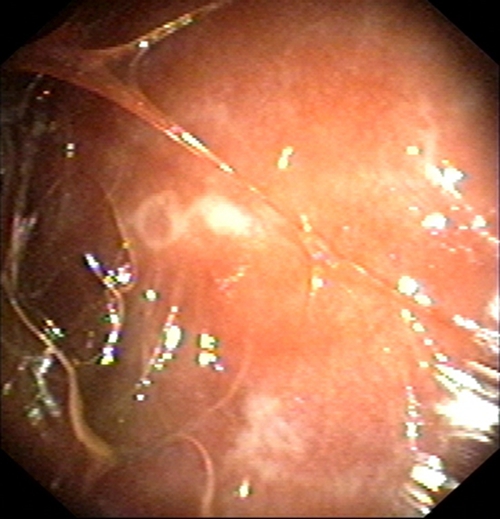

結核性胸膜炎胸腔鏡

結核性胸膜炎胸腔鏡的